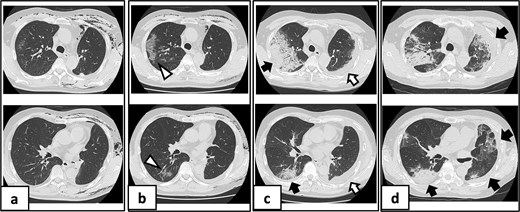

Serial chest imaging demonstrating pulmonary complications. (a) Postoperative day (POD) 10: Initial presentation without significant abnormalities. (b) POD 16: Peripheral ground-glass opacities (arrowheads). (c) POD 27: Patchy consolidation (solid arrows) with new ground-glass opacities and pleural effusion (open arrows). (d) POD 36: Progressive consolidation (solid arrows).

On POD 27, he was readmitted with fever (38.2°C) and respiratory failure. COVID-19 testing was negative. Chest computed tomography revealed patchy consolidations mixed with ground-glass opacities in the right upper lobe with notable expansion, and new ground-glass opacities in the right middle lobe and residual left upper lobe periphery (Fig. 2c). Findings excluded recurrent air leak or aspiration pneumonia. Despite antibiotic therapy, oxygen requirements increased to 2 L by POD 29.

Methylprednisolone pulse therapy (1 g/day for 3 days) was initially administered, followed by oral prednisolone (30 mg). However, oxygen requirements increased to 4 L on POD 31 (Fig. 3). On POD 36, a second methylprednisolone pulse course was initiated with cyclosporine A (150 mg) owing to progressive consolidation on chest imaging (Fig. 2d). Oxygen support was discontinued by POD 38, and he was discharged on POD 52. Follow-up image on POD 104 showed substantial radiological improvement (Fig. 4). Immunosuppressive medications were successfully tapered and discontinued by POD 329. This case was diagnosed as delayed-onset OP as a manifestation of post-acute COVID-19 syndrome, characterized by the biphasic clinical course and distinctive radiological progression occurring weeks after acute COVID-19 infection.